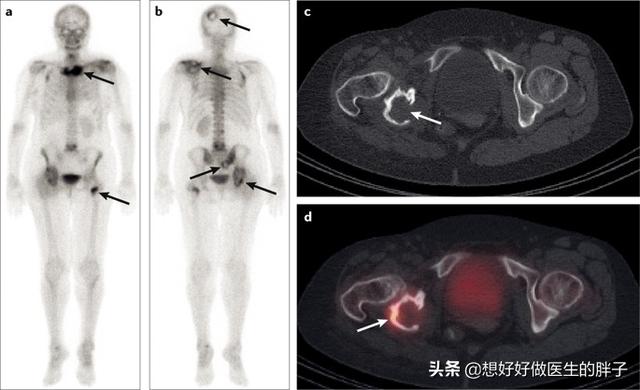

Quels sont les symptômes des métastases osseuses ? Le premier symptôme est la douleur. Le site de la métastase osseuse ressentira une douleur due à la destruction de l'os, qui peut ne pas présenter de symptômes évidents ou une douleur intermittente au début, mais comme la tumeur détruit l'os normal de manière progressive et s'aggrave peu à peu, la douleur dans le site métastatique s'aggravera également progressivement. Sur le plan clinique, il arrive que nous rencontrions un cas de douleur osseuse dans une certaine partie du corps, qui résulte d'une métastase osseuse d'une tumeur maligne. Il y a quelque temps, j'ai rencontré un cas, 40 ans, douleur à l'épaule, j'ai pensé à une épaule gelée, j'ai frotté quelques jours d'huile médicinale sans voir d'amélioration, mais de plus en plus de douleur, alors je suis allé à l'hôpital pour un examen, j'ai fait une imagerie par résonance magnétique, l'omoplate a été mangée par un morceau de (tumeur), considérant qu'il s'agissait d'une métastase osseuse, puis j'ai fait un scanner thoracique, un nodule dans le poumon droit, puis j'ai fait une biopsie pour faire la pathologie, qui était une métastase osseuse d'un cancer du poumon. Les informations sont les suivantes.

Sur le site des métastases osseuses, étant donné que le tissu osseux normal est détruit et remplacé par du tissu tumoral et que les cellules tumorales prolifèrent constamment, des ombres de masses de tissus mous peuvent être observées sur de nombreux sites de métastases osseuses, et peuvent être palpées si la masse se trouve dans une zone superficielle. En outre, l'érosion du tissu osseux normal par le tissu tumoral entraîne également la destruction et l'affaiblissement de la structure osseuse normale, de sorte que des fractures peuvent se produire sous l'effet de forces externes normales, appelées fractures pathologiques (figure ci-dessous). Outre la douleur et la fracture pathologique, les métastases au niveau de la colonne vertébrale peuvent également se manifester par une compression des racines nerveuses de la colonne vertébrale avec des symptômes tels qu'une déficience sensorielle, une faiblesse musculaire et, dans certains cas, une hypercalcémie.

Pour les patients sans antécédents de cancer, et si la famille est financièrement aisée, il est recommandé de réaliser un examen PET-CT pour rechercher des lésions cancéreuses suspectes sur l'ensemble du corps, ce qui permet de déterminer de manière adéquate la présence de lésions tumorales, leur degré d'évolution et le type de foyers métastatiques qu'elles présentent.

En cas d'antécédents de cancer et si le degré de malignité est jugé élevé à l'époque, il est possible de déterminer la présence de métastases osseuses par une scintigraphie osseuse du corps entier. Parallèlement, le degré de destruction osseuse au niveau du site de la métastase peut être clarifié par un examen par résonance magnétique.

La douleur est le premier symptôme de la plupart des métastases osseuses, >80%, et certaines métastases se manifestent à un très jeune âge. La scintigraphie osseuse (ECT) peut être pratiquée en cas de cancer du sein avec suspicion de métastases osseuses (douleur osseuse, fracture, élévation des phosphatases alcalines, hypercalcémie, etc. Certaines études ont montré que la TEP/TDM a une sensibilité similaire et une spécificité supérieure à celle de l'ECT et qu'elle peut être utilisée pour suivre l'évolution de la maladie après le traitement des métastases osseuses du cancer du sein. Si le diagnostic est difficile, un morceau d'os peut être prélevé pour un examen pathologique si nécessaire.